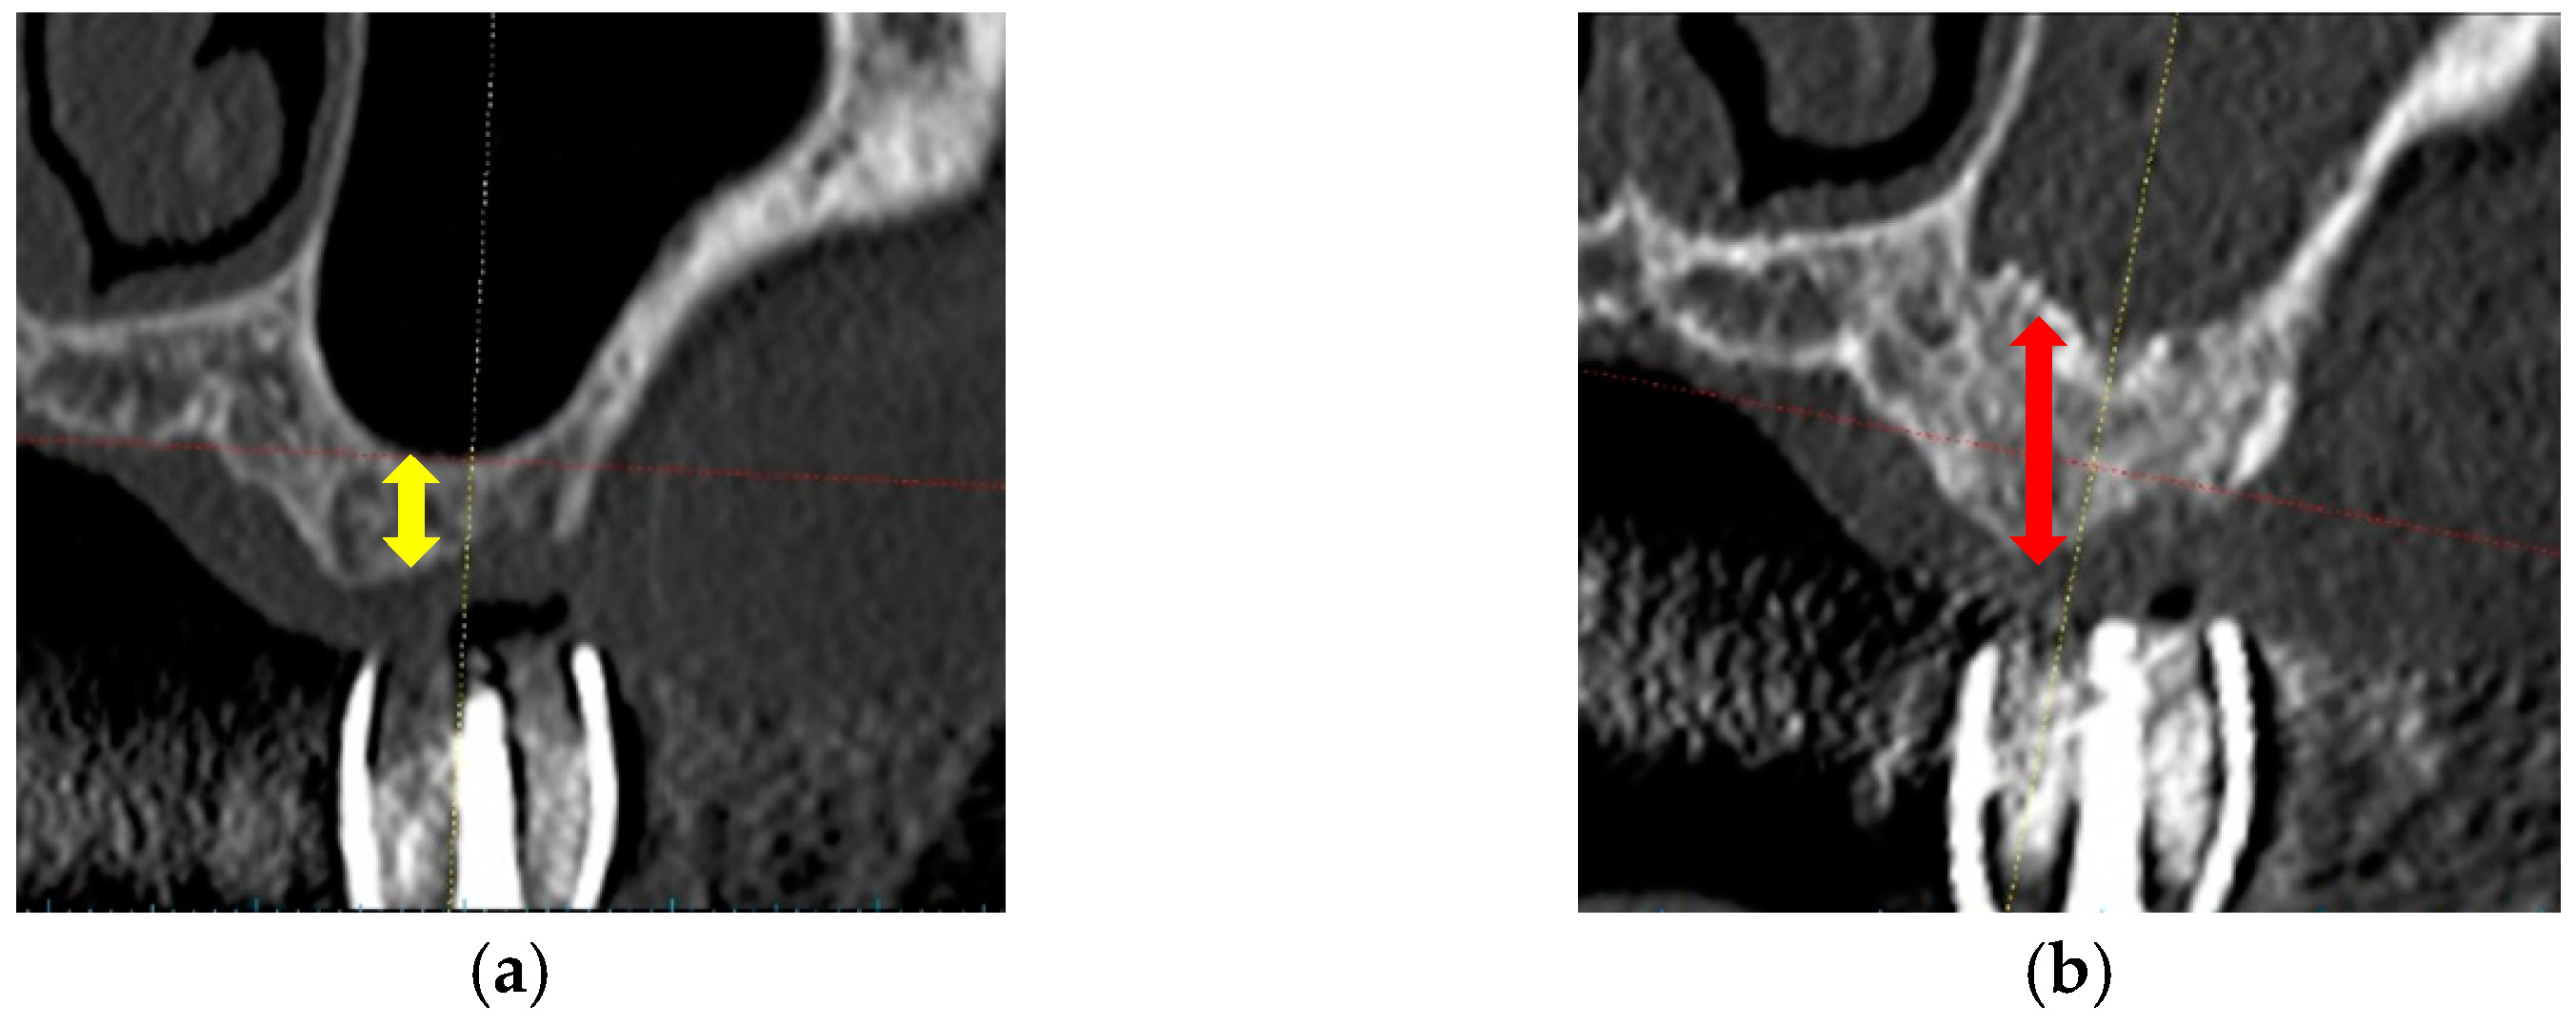

During SFE, no perforation of the sinus membranes was detected. The CT images (frontal views) of pre-SFE and pre-implantation are shown in Figure 3. Table 2 also presents SFE sites and vertical bone heights measured using pre-SFE and pre-implantation CT images. The mean increase of bone height after SFE with CO3Ap graft was 7.1 ± 2.4 mm (mean ± standard deviation (SD)). They revealed that the CO3Ap graft could maintain the vertical height and the space between the elevated sinus membrane and sinus floor. The amounts of CO3Ap granules used for SFE are also presented in Table 2.

Figure 3.

CT images of pre-SFE and pre-implantation. (a) Pre-SFE (frontal view), the yellow allow shows pre-vertical bone height; (b) Pre-implantation (frontal view), the red allow shows post-vertical bone height.

This clinical trial was planned to measure the vertical height at implant site (indicated by a diagnostic stent in CT image) to assess the result of SFE. The mean value of vertical bone height prior to SFE was 3.5 ± 1.3 mm. All sites were less than 6 mm and 10 sites were less than 4 mm, which were recommended to receive delayed implant placement [9,30,31]. CT images revealed that CO3Ap granules worked effectively as a graft material in SFE and as materials for space maintenance and new bone formation (7.1 ± 2.4 mm). However, future CT evaluation of three-dimensional mineralization after SFE (vertical and horizontal dimension) would be favorable. The histological analyses showed new bone formation and bone mineralization. The formation of osteoid around residual CO3Ap granules, which was similar to newly formed bone, suggested the capacity for bone formation by CO3Ap granules. ITVs revealed the primary stability in all cases. In addition, all implants and prostheses functioned uneventfully after 3-year functional loading (survival and success rates: 100%) and these results suggested the availability of CO3Ap granules as a graft material in SFE and delayed implant placement.